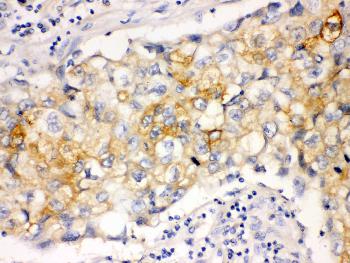

Figure 1: Anti-Involucrin antibody(39-1063). IHC(P): Human Lung Cancer Tissue.

Western blot : 2μg/ml; Immunohistochemistry(Paraffin-embedded Section) : 0.4-1μg/ml; Immunohistochemistry(Frozen Section) : 0.4-1μg/ml; Immunocytochemistry : 1μg/ml